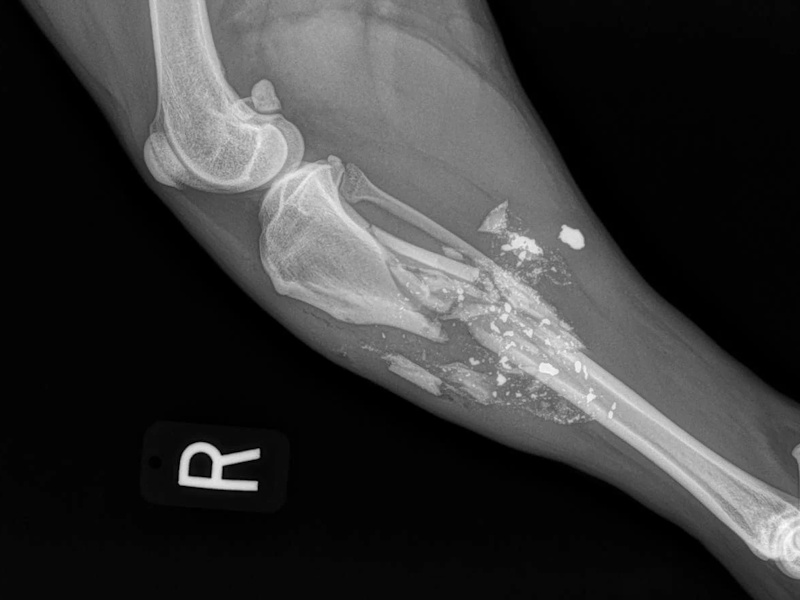

Fore Limb (Humerus, Radius/Ulnar, Metacarpus)